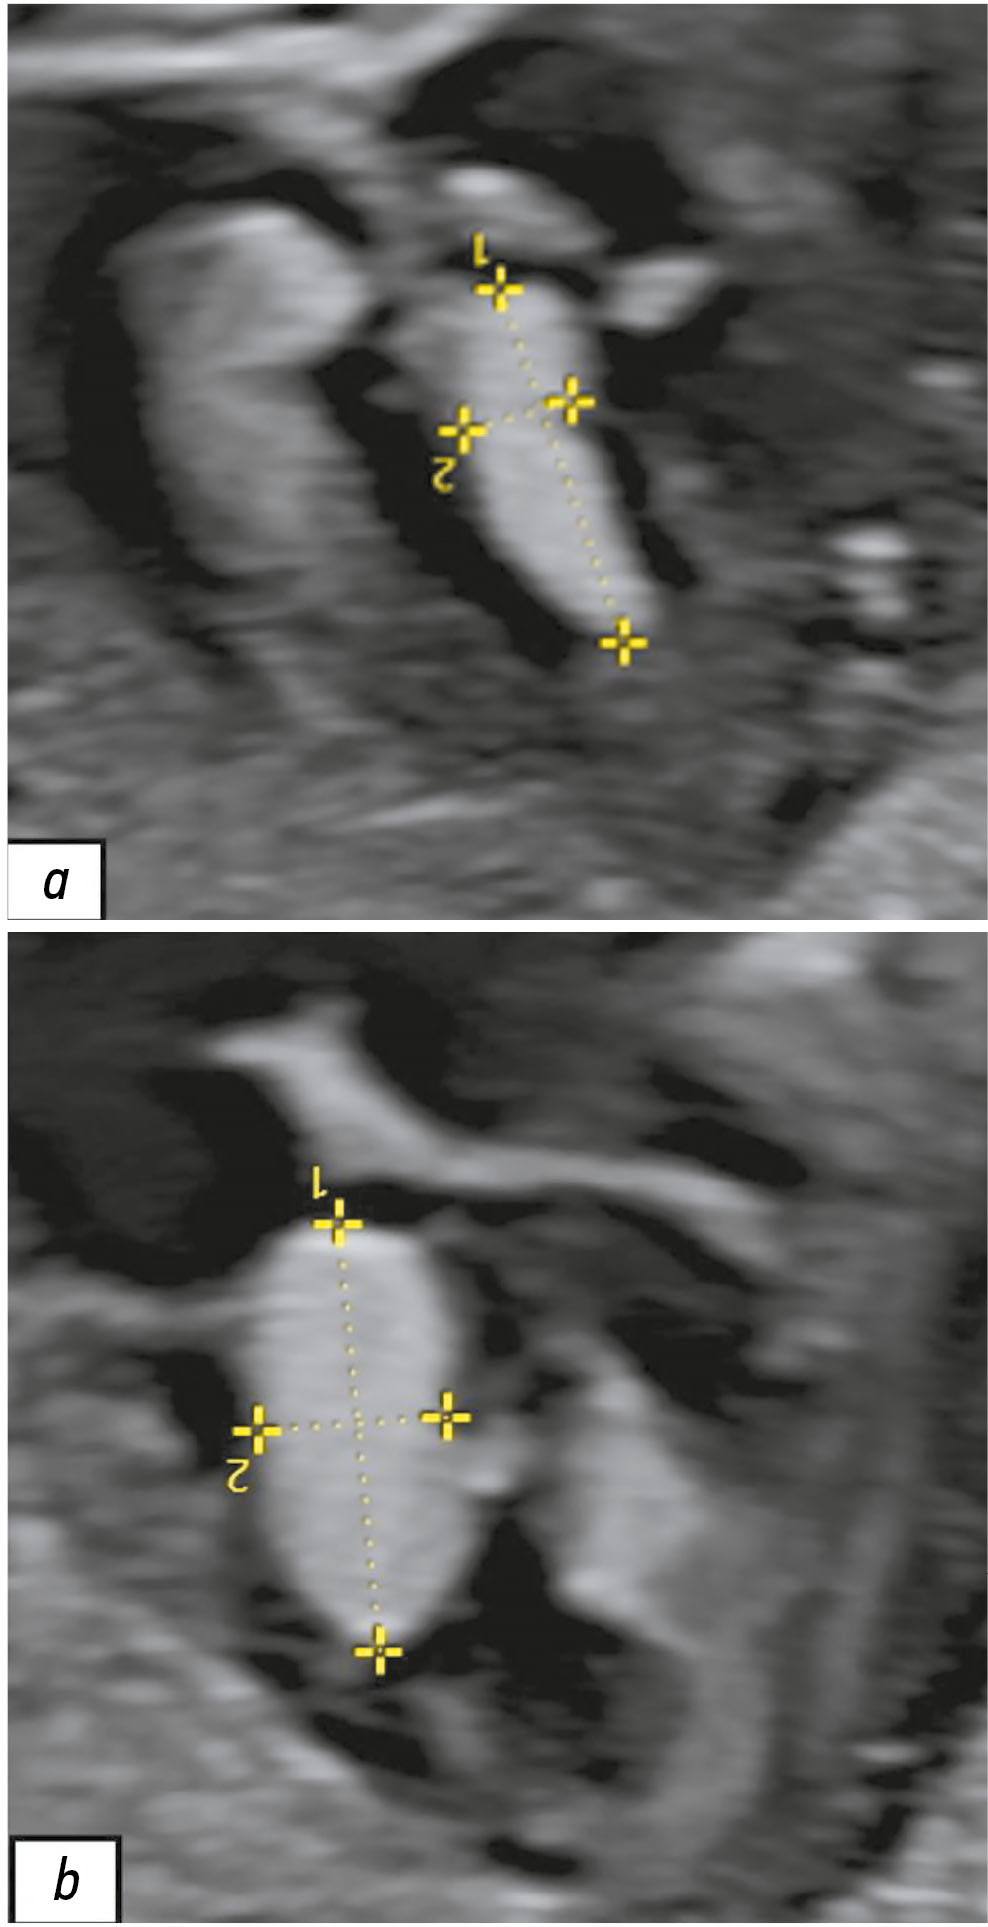

Hypophysitis is a rare inflammatory disorder that affects the pituitary gland and infundibulum, stems from autoimmune, infiltrative, infectious, or unknown causes. Its clinical diagnosis can be challenging because several pituitary lesions, including adenomas and metastases, may clinically present with similar characteristics. Magnetic resonance imaging is crucial for diagnosing suspected cases of hypophysitis and categorizing them as adenohypophysitis (anterior pituitary gland involvement) or infundibulo-neurohypophysitis (pituitary stalk and posterior pituitary involvement). Hypophysitis can be categorized as primary (autoimmune) or secondary due to local lesions (e.g., granulomas, cysts, adenomas) or systemic diseases (e.g., sarcoidosis, Wegener’s granulomatosis). Different factors may have impact on clinical course of hypophysitis. Among them background treatment. These cases have not been sufficiently studied and are practically not presented in publications.

A 37-year-old female with a history of hyperprolactinemia was being treated symptomatically with cabergoline. At first magnetic resonance imaging heterogeneity of the hypophysis was revealed. In September 2021 the follow-up magnetic resonance imaging revealed an increase in the size and heterogeneity of the pituitary gland. In December 2021, the patient developed severe COVID-19-associated pneumonia and was treated with corticosteroids and oxygen support. In May 2022 magnetic resonance imaging revealed a marked increase in the size and heterogeneity of the pituitary gland. Significant clinical and radiological improvement were stated after adding prednisone (10 mg in the morning and 5 mg in the evening) to her treatment.